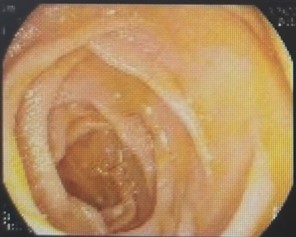

面对如此紧急的情况,干部保健病区冯建军主任联合消化内科赵刚副主任迅速启动了绿色通道,为刘爷爷进行了初步的稳定治疗,同时召集多学科专家进行紧急会诊。专家们一致决定先进行胃镜检查,了解患者既往手术方式,同时为可能的ERCP操作进行“探路”。后经胃镜检查,明确老人确实为“毕Ⅱ式远端胃部分切除”术后改变,内镜下反复寻找后,终于找到输入袢肠管以及十二指肠主乳头,同时为了后续手术时便于再次寻找,以一枚金属夹在十二指肠主乳头旁侧进行标记。